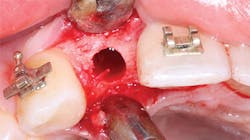

Figure 3: What resistance will this osteotomy provide to implant placement? Assuming the clinician has set the torque of the implant placement motor correctly, and the implant goes into the bone with the amount of torque at which the motor is set, the clinician may make a good estimation about the timing for implant loading.

These above suggestions are some of the same criteria that guide the implant-placing dentist who gives you loading suggestions. However, if you are not placing the implants, you do not have the opportunity to evaluate the bone condition at the time of implant placement (figures 3 and 4). The following topics are a few factors or techniques that can help you decide when to load the implant: